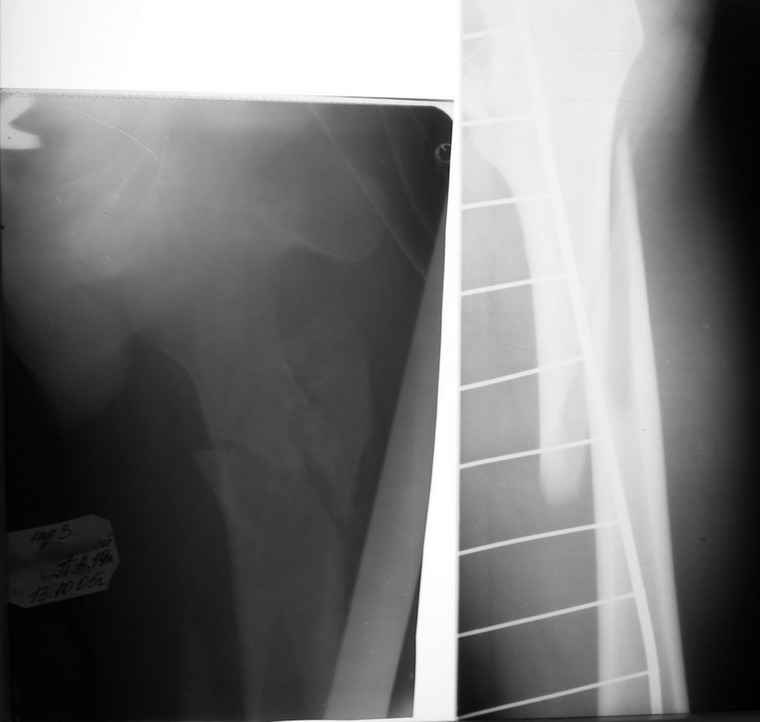

Если снимок справа по хронологии последний, то в тазобедренном сустава наступил анкилоз. Это хороший плюс костной ткани для постановки чашки эндопротеза, но отсутствие сохранения биомеханической оси бедренной кости ставит под вопрос благоприятный вариант усановки ножки эндопротеза.... Учитывая выполненную остеотомию, не считаю выполнение скелетного вытяжения лишенным смысла, для восстановления оси конечности с последующим, возможно, индивидуальным эндопротезированием.

Очень признателен Вам за ответ, но позвольте мне не согласиться с Вами. Я бы пока не делал вывод о анкилозировании тазобедренного сустава. На рентгеновских снимках, да и по данным компьютерной томографии (а этот метод один из самых современных и информативных), хорошо прослеживается постоянной ширины щель между головкой бедренной кости и вертлужной впадины. Кроме того, несложно увидеть разницу "шеечно-диафизарного угла" до и после выполнения тракции в аппарате. Хотя, Алексей, даже если я и прав, это не сильно облегчает нашу задачу.

Вот снимки по свежей ситуации, парень 19 лет, длинный оскольчатый перелом бедра от шейки до в-с/3. давно уже ходит на своих ногах.

Представленные Вами рентгенограммы действительно являются примером качественной фиксации спице-стержневым аппаратом. Они, как ни что другое, многое иллюстрируют.